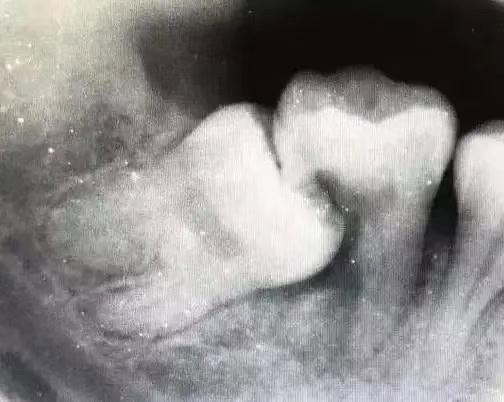

阻生嘅智齒會對第二磨牙施加壓力,導致第二磨牙嘅位置發生改變,甚至傾斜,影響咬合關係同整體牙列美觀。

2. 龋齒(蛀牙)

智齒同第二磨牙之間嘅狹窄空間容易積聚食物殘渣同細菌,形成盲袋,增加第二磨牙遠中(靠近智齒一側)面發生齲齒嘅風險。尤其當智齒只有一部分露出,更易藏污納垢。

4. 牙根吸收

阻生智齒嘅牙冠或牙根可能會直接接觸到第二磨牙嘅牙根,造成第二磨牙嘅牙根吸收,長遠來講會影響第二磨牙嘅穩定性,甚至令其鬆動或喪失。